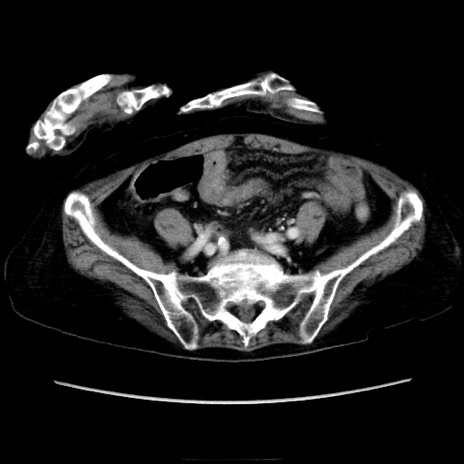

症例40(横断像)

【症例】90歳代女性

【主訴】腹痛・嘔吐

【現病歴】 食欲低下、嘔吐があり昨日他院受診。肺炎と診断され入院となる。入院後より腹部全体に圧痛あり。胃管留置され経過みていたが、症状持続するため、

当院転院となる。

【既往歴】胸椎圧迫骨折、胆石症

【身体所見】腹部:中央に激痛あり、圧痛あり、反跳痛不明

【データ】WBC 17100、CRP 18.82

横断像